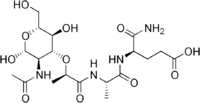

| IUPAC name

(4R)-4-[ [(2S)-2-[ [(2R)-2-[(2R,5S)-3-acetamido-2,5-dihydroxy-6-(hydroxymethyl)oxan-4-yl]oxypropanoyl]amino]propanoyl]amino]-5-amino-5-oxopentanoic acid | |

Acetylmuramyl-Alanyl-Isoglutamine | |

| C19H32N4O11 | |

| Molar mass | 492.47758 |

Muramyl dipeptide is a component of bacterial peptidoglycan, a recognition structure or activator for nucleotide-binding oligomerization domain 2 (NOD2) protein.[1] It is a constituent of both Gram-positive and Gram-negative bacteria composed of N-acetylmuramic acid linked by its lactic acid moiety to the N-terminus of an L-alanine D-isoglutamine dipeptide.[1] It can be recognized by the immune system as a pathogen-associated molecular pattern and activate the NALP3 inflammasome which, in turn, leads to cytokine activation, IL-1α and IL-1β especially.[2]